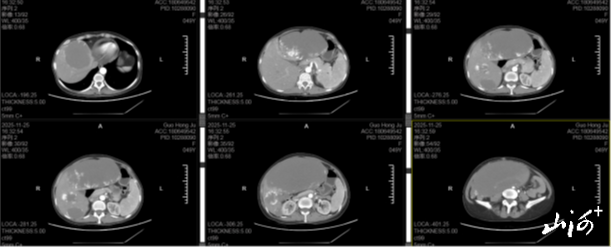

“患者就诊时肚子胀得像怀了胎儿,疼得直皱眉。”回忆起当时的情况,临汾市人民医院肝胆胰外科医生温江涛仍记忆犹新。腹部CT结果让所有人都捏了把汗——患者腹腔里几乎被一个巨型肝脏血管瘤占满了,直径约30× 25厘米,大小相当于一个小西瓜。这个“大家伙”死死压迫着下腔静脉、门静脉等关键血管,稍微一碰就可能破裂大出血,堪称一颗“定时炸弹”。

术前腹部CT

更棘手的是患者的身体状况。长期被肿瘤消耗,再加上腹腔被压迫导致吃不下饭、营养跟不上,她的血红蛋白只有69g/L,而正常女性的标准是120-150g/L,属于中度贫血,根本扛不住常规大手术。雪上加霜的是,血库同型血储备不足,要是手术中大量出血,连输血救急都成问题。